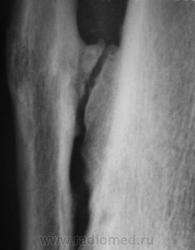

Пациент, в течение последних 2-х лет, жалуется на боли в нижней трети голени. Сегодня, хирургом, пациентка направлена на рентгенографию костей дистальной трети голени и голеностопного сустава. Что посоветуете уважаемые коллеги?

А что здесь советевать? Межберцовый неоартроз, вероятно, травматического генеза. Косой перелом н/л с признаками неполной консолидации. Попробуйте при производстве боковых снимков г/ст с-ва ( при травме) приподнимать пятку на 2-3 см.

Доброй ночи! Разволокнение коркового слоя, нечеткий очаг деструкции. Правда, нет секвестра. Если на увеличении не пригрезилось, то и линейный периостит. Вообще-то ответ был интуитивный, без логических обоснований. Ошиблась?